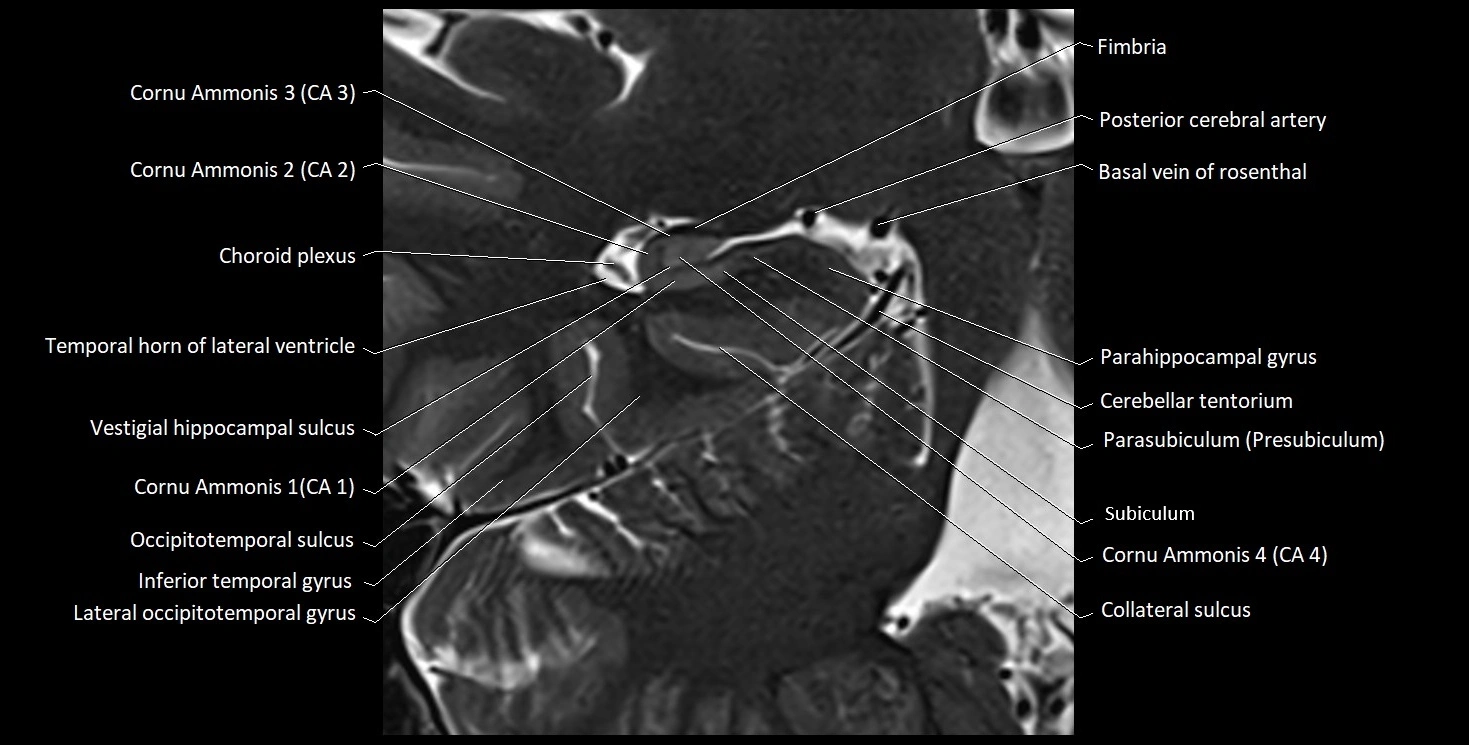

The alveus of the hippocampus is a thin, white matter layer covering the superior (ventricular) surface of the hippocampus within the temporal horn of the lateral ventricle. It consists of myelinated efferent fibers arising primarily from the pyramidal neurons of the hippocampus. These fibers converge medially to form the fimbria of the hippocampus, which continues posteriorly into the fornix, forming a crucial part of the Papez circuit involved in memory consolidation and emotional processing.

The alveus serves as the initial output pathway of the hippocampal formation, linking it to other limbic structures including the hypothalamus, mammillary bodies, and cingulate gyrus. Because of its intimate relationship with the hippocampal head and tail, it is often evaluated in cases of temporal lobe epilepsy, hippocampal sclerosis, and neurodegenerative diseases.

Location and Structure

• Position: Lies on the ventricular (superior) surface of the hippocampus, beneath the ependyma of the inferior horn of the lateral ventricle.

• Composition: A thin sheet of myelinated axons derived mainly from hippocampal pyramidal cells.

• Course: Fibers run medially along the hippocampal surface to form the fimbria of the hippocampus, which curves upward and backward into the fornix.

• Relations:

• Superiorly: Ependyma and CSF of the temporal horn of the lateral ventricle

• Inferiorly: Pyramidal cell layer of the hippocampus (CA1 region)

• Medially: Fimbria and fornix

• Laterally: Temporal lobe white matter and parahippocampal gyrus

MRI Appearance

T2-weighted images:

• Alveus: Low signal line overlying brighter hippocampal gray matter.

• CSF: Bright hyperintense.